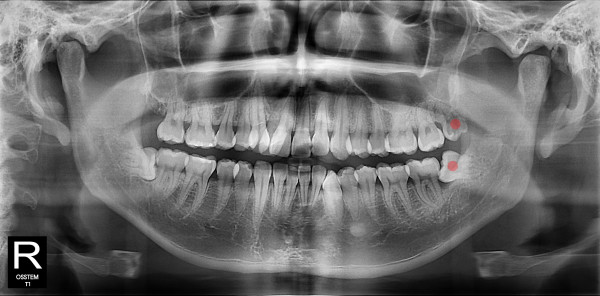

사랑니발치 20대/남성

ae27575af29d49719312fde5a1f0cca6_1764401746_6609.jpg